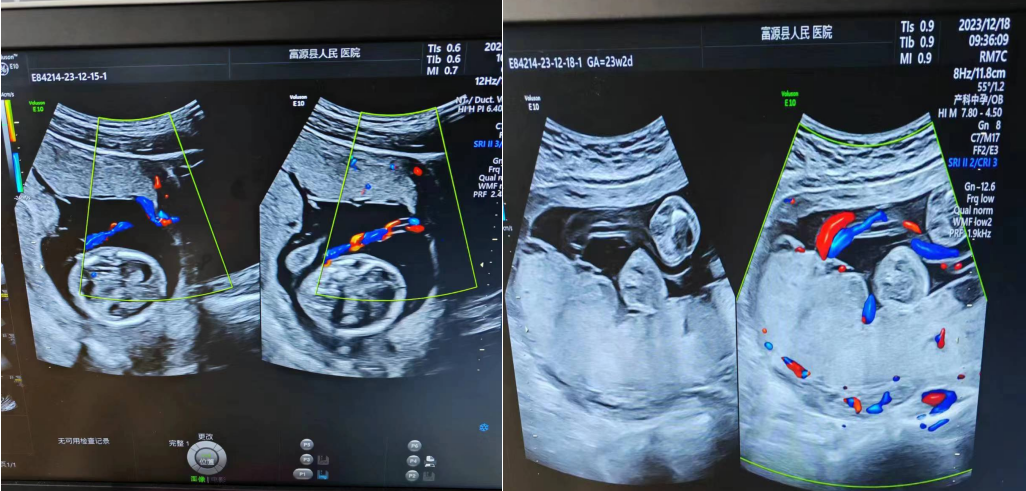

而真正的彩超指的是,彩色多普勒超声,是在二维超声的基础上,利用多普勒原理对检查部位的血流信息进行处理,直观地将血管中的血流信号以红、蓝等彩色来表示,并叠加在二维灰阶图像上实时地显示出来,能更好地显示组织内血流分布情况,并可判断血流方向、显示平均流速信息。